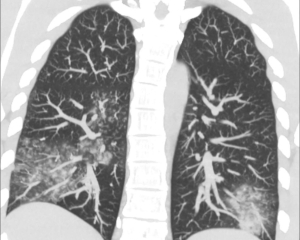

"Метапневмовірус - це вірус, який традиційно циркулює в Україні під час кожного епідемічного сезону. Його симптоми подібні до застуди чи легких випадків грипу: нежить, кашель, підвищена температура. У більшості випадків захворювання протікає легко й рідко викликає ускладнення", - повідомляє Центр громадського здоров'я.

Голубовська пояснює, що особливий ризик зараження мають діти, літні люди та пацієнти з ослабленою імунною системою. HMPV належить до тієї ж родини вірусів, що і респіраторно-синцитіальний вірус (RSV), і був виявлений у 2001 році.

"Вірус може спричиняти як легкі симптоми респіраторних захворювань, так і тяжкі випадки з розвитком дихальної недостатності. Зараження відбувається крапельним шляхом, а хвороба може повторюватись протягом життя. Інкубаційний період HMPV складає 3-6 днів, а тривалість захворювання варіюється від 7 до 10 днів. Для тяжких хворих у світі застосовують інгаляційний рибавірин. Водночас в Україні така форма препарату не зареєстрована", - зазначає Голубовська.